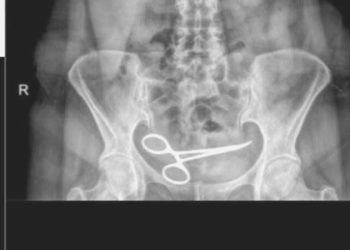

Read moreAnkara'da tedavi gördüğü özel hastanede yapılan ameliyattan yaklaşık 8 ay sonra şiddetli karın ağrısı şikayetiyle öteki bir hastaneye başvuran Şadiye ...